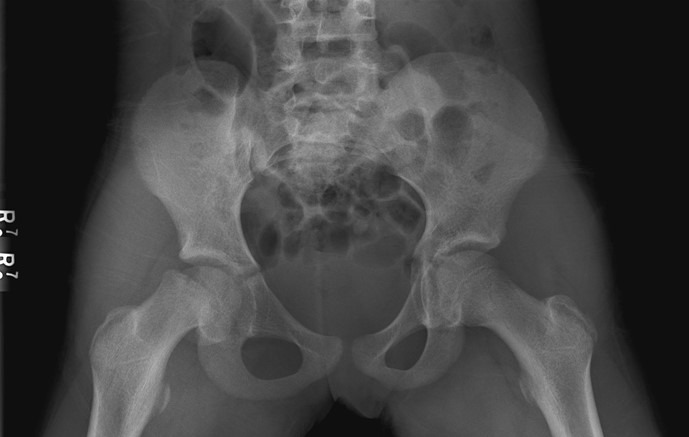

A 10-year-old girl is brought to the clinic for evaluation of a limp.  She first noticed mild pain in the right groin 2 weeks ago and took ibuprofen, which initially helped.  The pain acutely worsened 2 days ago after the patient fell while ice skating.  Since then, she has been unable to fully bear weight on her right leg due to pain, which is now minimally relieved with ibuprofen and rest.  The patient has autoimmune hypothyroidism for which she takes levothyroxine.  Temperature is 37.2 C (99 F) .  Height and weight are at the 10th and 25th percentiles for age, respectively.  When the right hip is flexed, there is external rotation of the hip.  When the left hip is flexed, the hip remains in a neutral position.  There is normal range of motion in both knees and no redness or edema overlying the hips and knees.  The patient has a limp and bears little weight on her right side when walking.  Bilateral hip radiograph with frog-leg lateral view reveals the following: A 10-year-old girl is brought to the clinic for evaluation of a limp.  She first noticed mild pain in the right groin 2 weeks ago and took ibuprofen, which initially helped.  The pain acutely worsened 2 days ago after the patient fell while ice skating.  Since then, she has been unable to fully bear weight on her right leg due to pain, which is now minimally relieved with ibuprofen and rest.  The patient has autoimmune hypothyroidism for which she takes levothyroxine.  Temperature is 37.2 C (99 F) .  Height and weight are at the 10th and 25th percentiles for age, respectively.  When the right hip is flexed, there is external rotation of the hip.  When the left hip is flexed, the hip remains in a neutral position.  There is normal range of motion in both knees and no redness or edema overlying the hips and knees.  The patient has a limp and bears little weight on her right side when walking.  Bilateral hip radiograph with frog-leg lateral view reveals the following:   Which of the following is the best next step in management of this patient? A) Closed reduction of the hip joint B) Oral methotrexate therapy C) Physis stabilization with screw fixation D) Rest and analgesics as needed E) Total joint replacement Which of the following is the best next step in management of this patient?